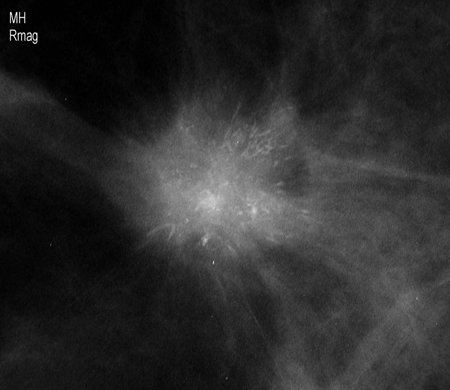

[Figure caption and citation for the preceding image starts]: Mamografia de rastreamento demonstrando massa mamáriaCortesia da Dra. Nancy Pile, Universidade de Louisville; usado com permissão [Citation ends].

[Figure caption and citation for the preceding image starts]: Visualização de magnificação demonstrando uma massa espiculada irregular com calcificações associadasCortesia da Dra. Nancy Pile, Universidade de Louisville; usado com permissão [Citation ends].